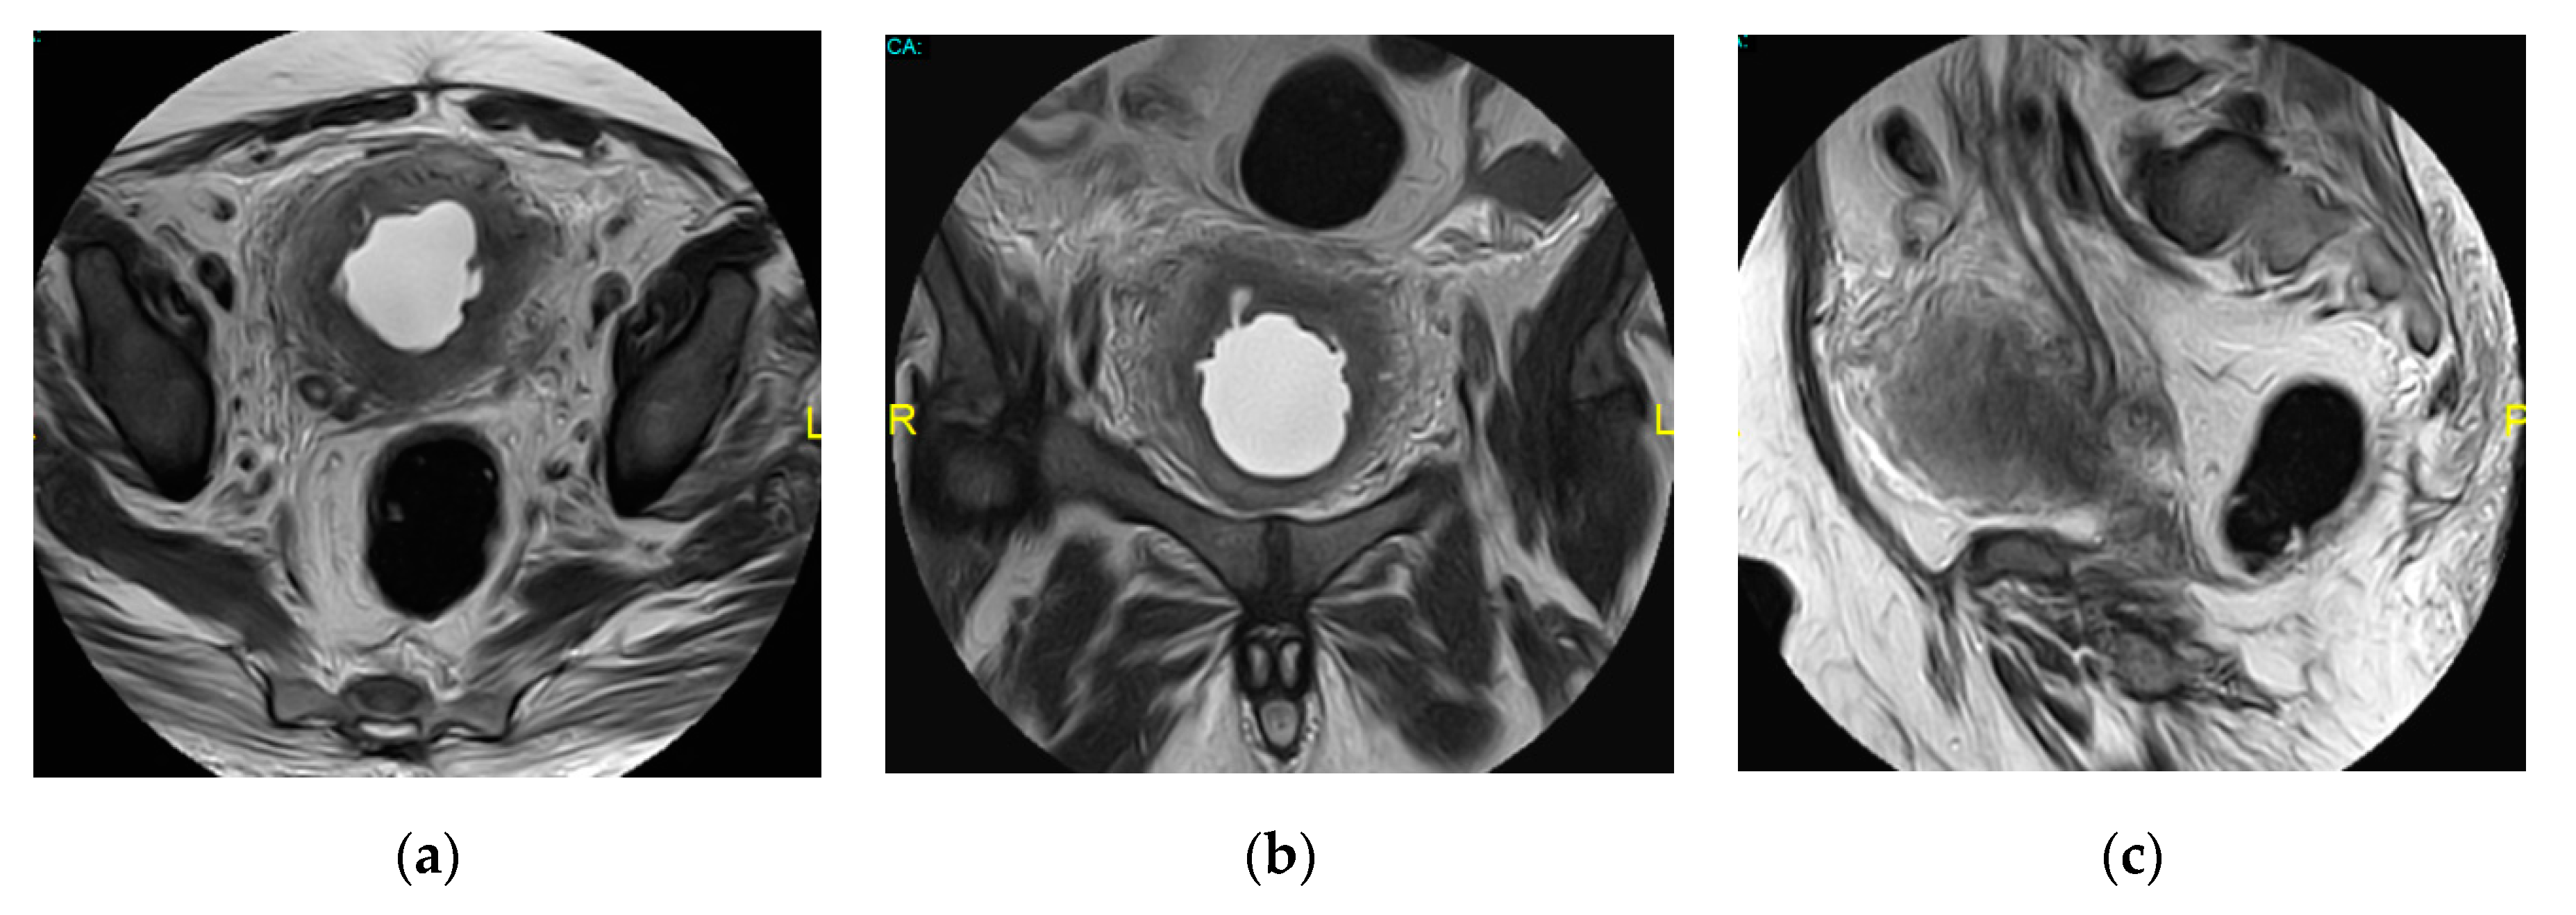

2.15. Acute Bacterial Prostatitis and Prostatic Abscess

| Prostatic abscess | Non enhancing fluid collection with peripheral or septal enhancement and non-enhancing central fluid. Possible extraprostatic extension |